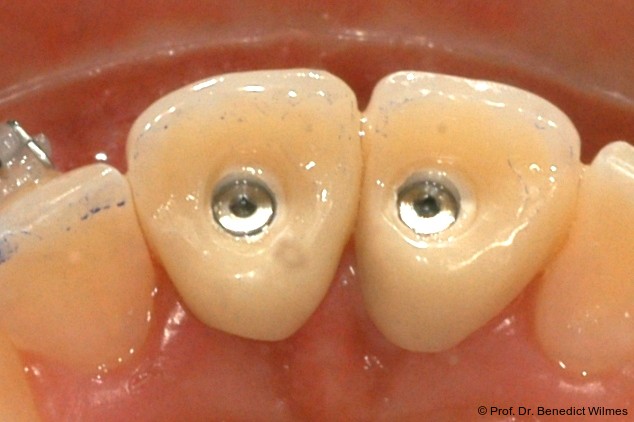

Bei einer elfjährigen Patientin fehlten bei Zustand nach Frontzahntrauma im Alter von neun Jahren beide oberen mittleren Schneidezähne (Abb. 8a+b). Als temporärer Ersatz wurden Miniimplantate (Abb. 9, 2 x 13 mm) eingesetzt und Kronen im Labor angefertigt, welche auf den Miniimplantaten verschraubt wurden (Abb. 10a+b). Die Miniimplantate wurden im Alter von 19 Jahren, also nach achtjähriger Nutzung (Abb. 11a+b), durch dentale Implantate ersetzt.